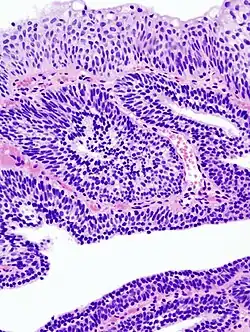

Photomicrographie d'un papillome malpighien sur une langue. Coloration à l'hématoxyline et à l'éosine.

- Papillome malpighien : composé d'axes conjonctifs bordés par des cellules malpighiennes, rappelant la structure des « papilles ». Ils peuvent former un relief à la surface ou s'invaginer dans la muqueuse (papillome inversé).